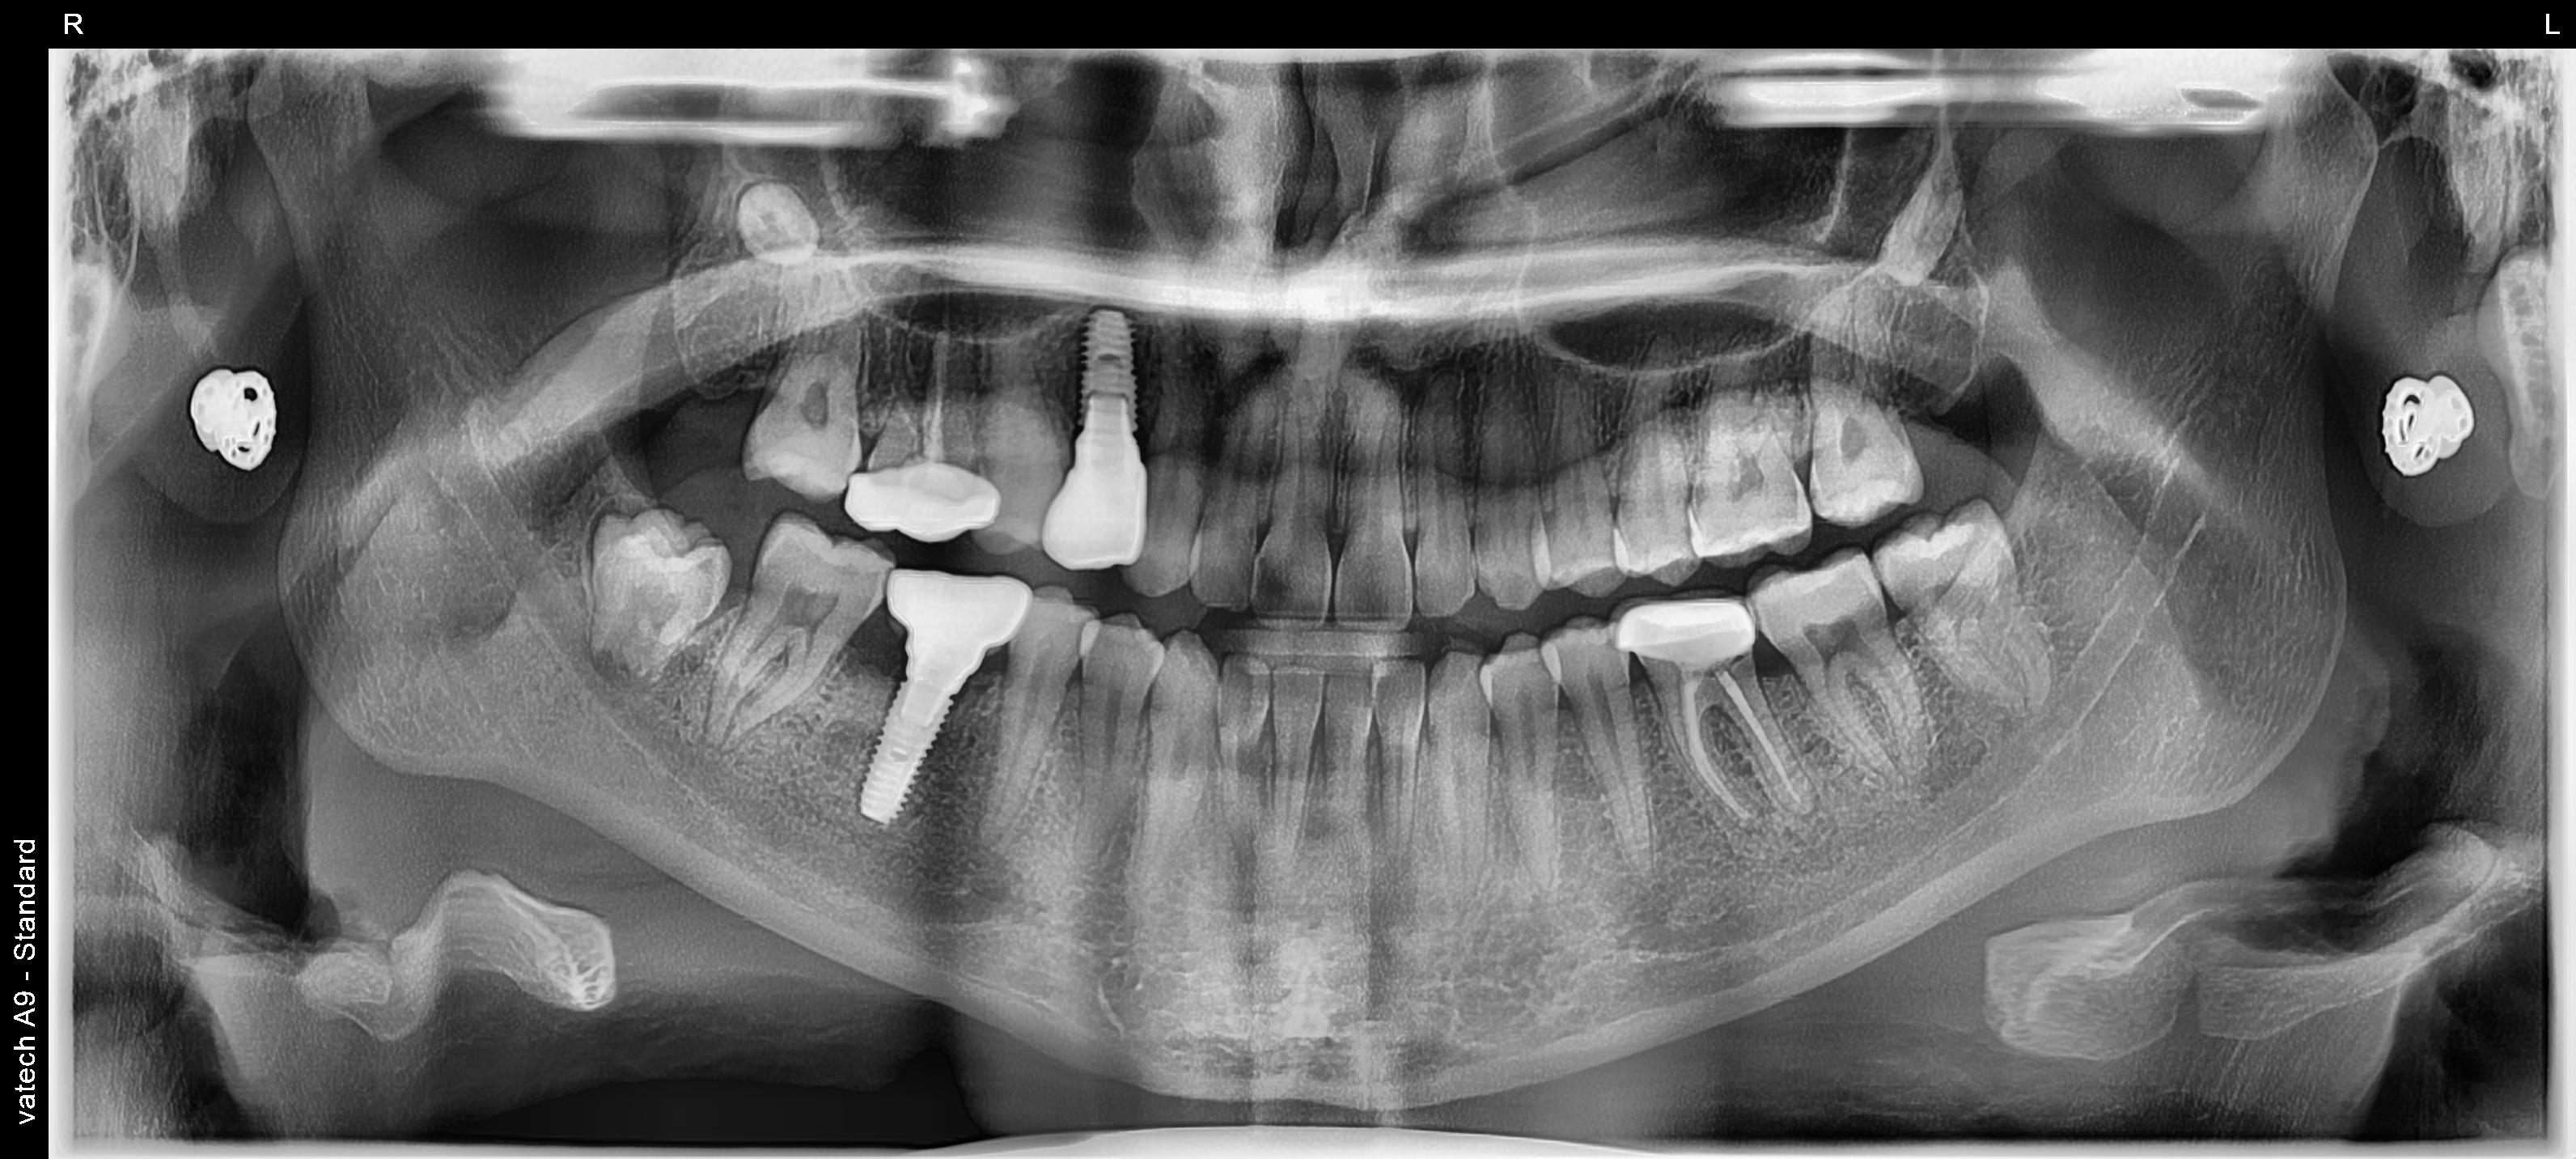

In dental implant cases, CT scans and bone grafting are sometimes required as part of the treatment. We perform a CBCT scan before the procedure to plan the implant precisely, and a post-operative scan to confirm accurate placement. In cases where bone support is insufficient, bone grafting may be needed to improve the long-term success of the implant. All of this is discussed in detail during your planning visit after the initial CBCT scan.

Digital CBCT Planning

3D imaging of your jaw

Helps assess bone quality and volume

Guided Implant Surgery

Implant placement is pre-planned digitally

A surgical guide ensures exact positioning

Real Case Examples From Beyond Dental Clinic, Delhi

Case 1: Single Tooth Implant

Implant: Osstem

Cost: ₹50,000 – ₹60,000

Bone graft (if needed): ₹5,000 – ₹10,000

Straightforward case with predictable outcome.

Case 2: Full Upper Arch Implant (Complex Case)

Patient condition:

Multiple missing and compromised teeth in the upper jaw

Reduced bone support in certain areas

Treatment approach:

Full upper arch rehabilitation

Multiple implants placed with guided surgery

Bone grafting in selected regions

Cost:

₹X,XX,XXX – ₹X,XX,XXX (varies based on implant type and grafting extent)

Outcome:

Restored function (ability to chew properly)

Improved aesthetics and smile

Stable, long-term solution

These cases require:

Detailed planning

Surgical expertise

Precise execution